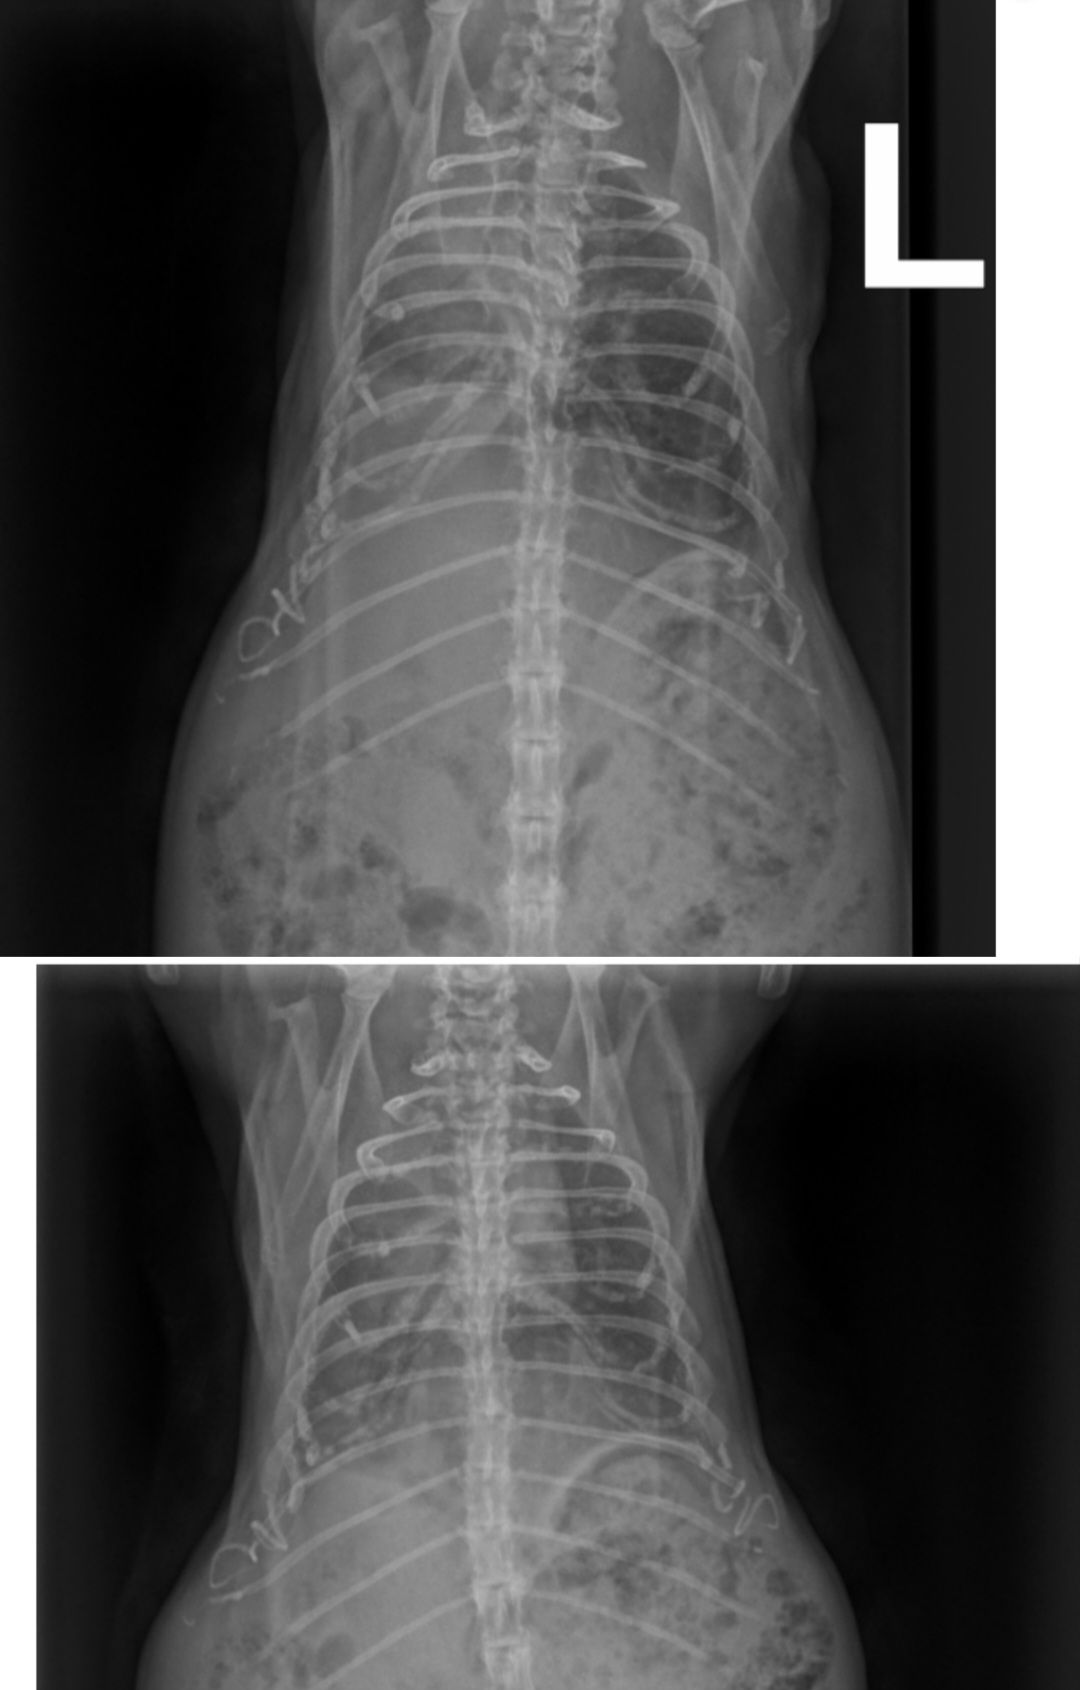

Auf dem ersten Bild fällt der große Unterschied zwischen dem auf dem Bild links zu sehenden Lungenflügel und dem anderen, weniger geschädigten auf. Johnny schien dort nach oder bei dem Einatmen aufgenommen worden zu sein.

Auf dem zweiten Bild schien er gerade ausgeatmet zu haben. Daher ist auch in dem besseren Lungenflügel weniger Luft als vorher. Aber der Unterschied zwischen bei Lungenflügeln ist geringer geworden. Zudem ist auf der auf dem Bild rechten Seite der Lungenflügel wieder gleichmäßiger "befüllt".

Die Heimtierärztin war heute nur im OP da, aber ich konnte Fienchen heute früh direkt zum Röntgen vorbeibringen und sie hat sich die Bilder kurz angeschaut und einen ersten Plan aufgestellt. Leider konnte ich nicht direkt mit ihr sprechen, aber morgen sollen wir wiederkommen, dann macht sie noch einen Ultraschall. Neben einer Aufgasung ist da nämlich noch eine Struktur im Bauchraum, die sie sich im Schall ansehen will.

Hat das von euch schon mal jemand gesehen? Könnte das die Blase und somit ein Stein sein? Und rechts unten davon auch was komisches(?)Ach Mäuschen... 🥺

Rechts unten würde ich zur Blase zuordnen und deshalb auf Blasengries oder Blasenschlamm tippen. Das oben könnte evtl. ein riesiger Blasenstein sein.

Das Auffällige auf dem Röntgenbild soll wohl eine Kalkablagerung sein (wo/von was konnte ich nicht mehr fragen) und vermutlich nur ein Nebenbefund, aber nicht die Ursache für ihren Zustand.

Lunge im Röntgenbild massiv angegriffen (ggf Entzündung aus Maul in die Lunge gewandert?), stark aufgegast, Untertemperatur, schwere Atmung.